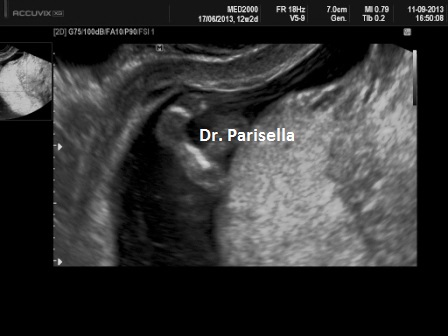

1) obliterazione della cisterna magna;

I primi tre segni (segno del limone, obliterazione della cisterna magna, cervelletto a banana), c.d. segni indiretti, hanno una elevata sensibilità nella diagnosi dei difetti aperti e sono espressione della sindrome di Chiari tipo 2. Questa è la conseguenza della perdita di liquido cefalo-rachidiano attraverso il difetto spinale; la diminuzione della pressione idrostatica provoca iposviluppo della fossa cranica posteriore con conseguente erniazione del tronco encefalico e del cervelletto che si piega assumendo il classico aspetto a banana. La perdita di liquido cerebrospinale attraverso il difetto spinale provoca un aumento dei livelli di alfa-fetoproteina nel liquido amniotico e nel siero materno.